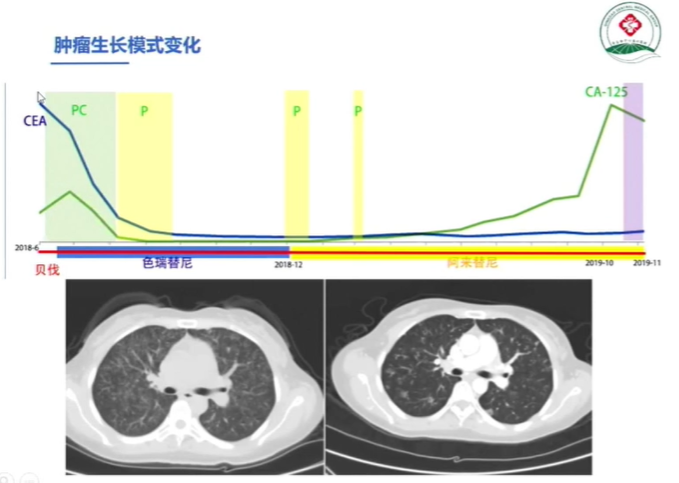

接下来,看一例其中的具体治疗案例患者基本信息

辅助检查情况如下

一线治疗方案:

在经过两轮治疗后患者病情进展后进行测序

但遗憾的是患者未能找到有效的驱动突变,因此在这样情况下考虑到ALK抑制剂仍然对患者有获益,后线治疗方案如下

在经过一段时间治疗后,患者出现治疗分离反应

(其颅内转移灶处于大PR状态,但肺部病灶从散点状变成弥漫状态)